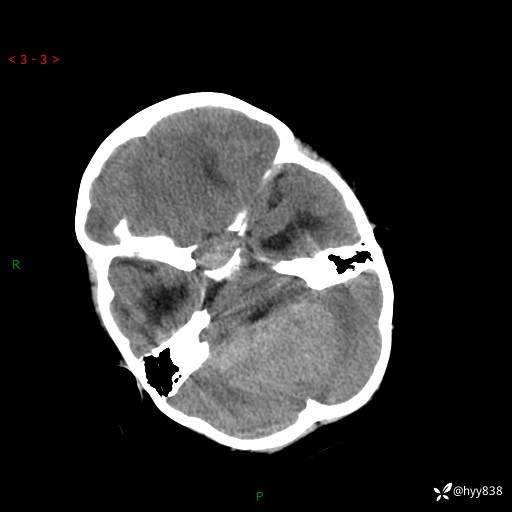

颅脑CT平扫

三脑室、四脑室多发病变,如何分析?

髓母细胞瘤 (13)